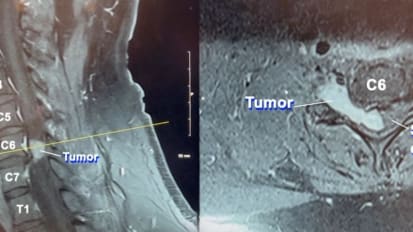

Challenging surgery removes dangerous, rare tumor from man’s spine News

Challenging surgery removes dangerous, rare tumor from man’s spine

Charles Lavender’s surgery in April 2023 to remove a cervical intradural traumatic neuroma from his neck lasted 11 hours. The tumor, pressing dangerously on his spinal cord, was exceedingly rare, based on its location, pathology, and the patient’s history.